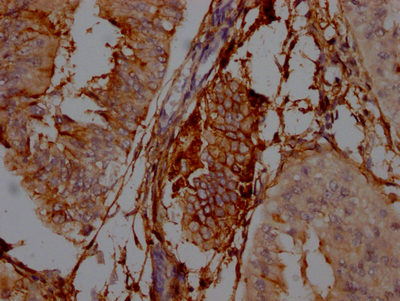

IHC image of CSB-RA978310A0HU diluted at 1:100 and staining in paraffin-embedded human endometrial cancer performed on a Leica BondTM system. After dewaxing and hydration, antigen retrieval was mediated by high pressure in a citrate buffer (pH 6.0). Section was blocked with 10% normal goat serum 30min at RT. Then primary antibody (1% BSA) was incubated at 4℃ overnight. The primary is detected by a Goat anti-rabbit IgG polymer labeled by HRP and visualized using 0.05% DAB.

IHC image of CSB-RA978310A0HU diluted at 1:100 and staining in paraffin-embedded human colon cancer performed on a Leica BondTM system. After dewaxing and hydration, antigen retrieval was mediated by high pressure in a citrate buffer (pH 6.0). Section was blocked with 10% normal goat serum 30min at RT. Then primary antibody (1% BSA) was incubated at 4℃ overnight. The primary is detected by a Goat anti-rabbit IgG polymer labeled by HRP and visualized using 0.05% DAB.